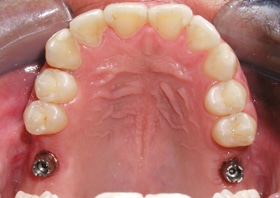

Pablo lost his back molars to gum disease. After repairing the damage to his bone, we placed dental implants to permanently support new molars and let Pablo eat normally again.